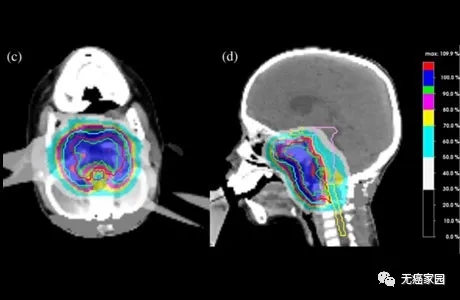

图像取自“点扫描质子放射疗法

质子治疗的更高精确度使健康器官不受影响,允许更高剂量的辐射传递到颅底肿瘤。剂量越高,肿瘤控制得越好。

在目前的情况下,质子治疗能够实现更好的肿瘤覆盖率,大约为99%(规定剂量为72 Gy),而光子治疗为91%。相比之下,质子治疗对脑干的最大剂量为57 Gy,光子治疗计划为63 Gy。质子计划实现的脑干平均剂量为4.8 Gy,显著低于光子治疗的24 Gy。

上图:质子治疗的辐射覆盖范围;没有出口剂量;下图:光子疗法的辐射覆盖率;存在出口剂量该患者在8周内接受了40质子放射治疗分数的72Gy的生物等效剂量。没有给予额外的全身治疗。患者对药物的耐受性良好,毒性有限,目前正接受常规随访。